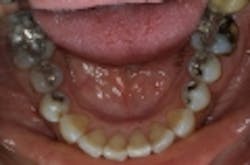

Adam Yauch of the Beastie Boys lost his battle to cancer last week. Where did his cancer start? In his parotid gland. It's a gland located below the earlobe, and is one of three major salivary glands in the head and neck. Although, it is an extremely rare cancer, and it mostly affects patients 55 and older, it is still prevalent among a large populous. Michael Douglas, another high profile patient, has been undergoing treatment, in recent months, for oral cancer, which started at the base of his tongue.Despite the fact that more media attention spotlights oral cancer when celebrity patients are its victims, the number of Americans dealing with oral cancer are staggering. According to Velscope.com, approximately 36,540 Americans were estimated to be diagnosed with cancer of the oral cavity and pharynx in 2010. During the same time period 7,880 Americans were estimated to succumb to it.Salivary glad cancer along with other more common oral cancers can be prevented if diagnosed early. Aside from tobacco use and alcohol, the fastest growing risk factor for this disease is infection with the Human Papilloma Virus (HPV). However, oral cancer caused by HPV has a higher survival rate than those cancers caused by smoking or tobacco use.So how can oral cancer be detected early? Patients should regularly visit their dentist and have him or her do a routine oral head and neck exam. In fact, that should be part of every new patient or six month recall exam. Incipient oral cancer lesions, if detected early, can be removed to stop their spread. Common areas of oral cancer lesions etiology include the tongue, the inner lip, and the roof of the mouth.Even though heightened attention is turned to oral cancer when celebrities are affected, the stats speak loudly. One American dies every hour due to this disease. More needs to be done to stop its spread and prevent its start.Editor's Note: Iman Sadri is a cosmetic dentist and writer based in Irvine, California.